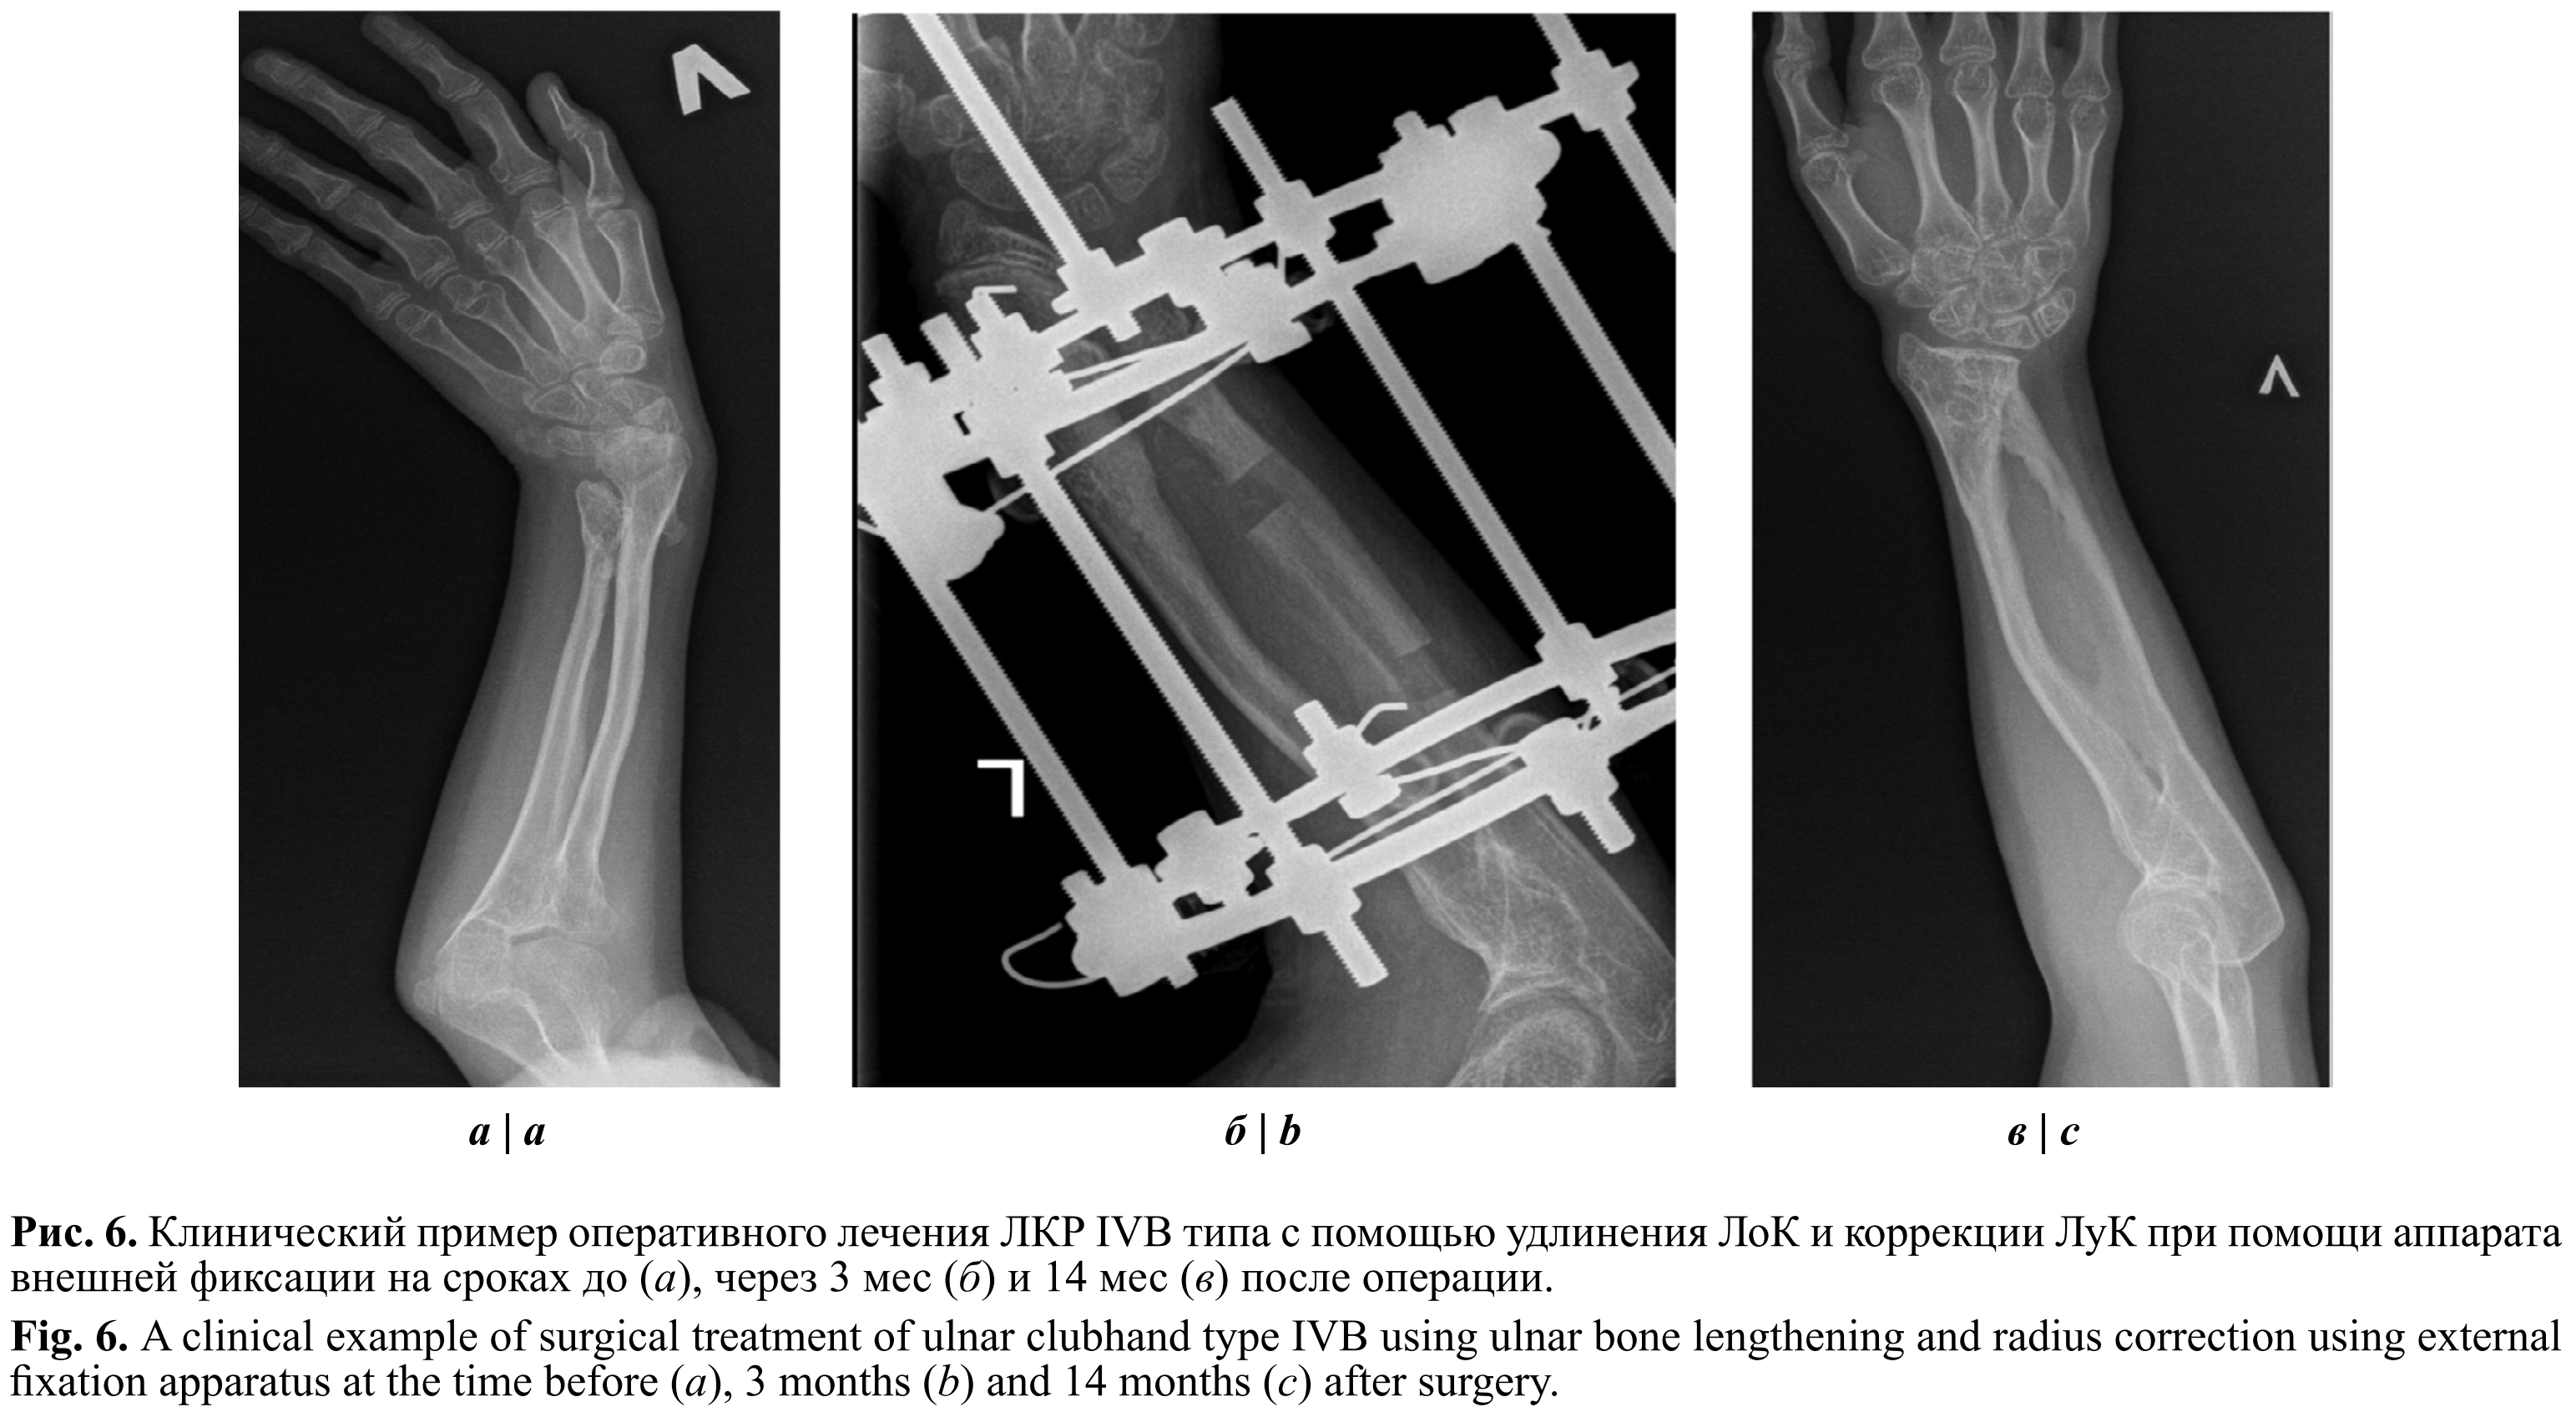

Больной В., 12 лет, диагноз: множественная наследственная экзостозная хондродисплазия, двусторонняя ЛКР тип IVB. ЛКР начала формироваться с 7 лет. Ранее проводились этапные вмешательства по удалению остеохондромных образований нижних конечностей, коррекция вальгусной деформации левой бедренной кости.

Локально: ось верхних конечностей — локтевая девиация кистей больше слева. Движения в плечевых и локтевых суставах в полном объёме с двух сторон. Супинация — до 55° слева и до 70° справа (умеренное ограничение при норме 80–90°), пронация 75° с двух сторон. Ограничение лучевой девиации в кисти до 10° справа, до 20° слева. Сгибание и разгибание в лучезапястных суставах без ограничений. Пальпаторно определяются единичные остеохондромные образования в дистальной трети костей предплечий с двух сторон.

При рентгенографии костей правого предплечья в прямой проекции UT 40°, RAA 38°, LS 14 мм, PUL 0,89 (рис. 6). Больному было проведено оперативное лечение: удлиняющая остеотомия правой ЛоК и корригирующая остеотомия ЛуК с фиксацией в аппарате внешней фиксации, краевая резекция остеохондром ЛуК. На контрольной рентгенограмме костей правого предплечья в прямой проекции через 18 мес UT 28°, RAA 34°, LS 11 мм, PUL 1,09. Достигнута удовлетворительная степень коррекции.